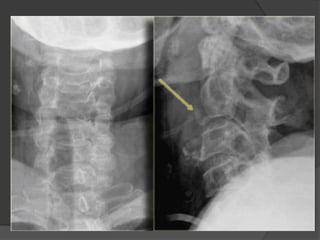

Flexion Teardrop Fracture C5-6

fracture is the result of a combination

of flexion and compression ,most commonly at C5-6

 The teardrop fragment comes from the

anteroinferior aspect of the vertebral body. The

larger posterior part of the vertebral body

is displaced backward into the spinal canal.

Best seen on lateral view

 It is an completely unstable fracture associated with

complete disruption of ligaments and anterior cord

syndrome and quadriplegia

 70% of patients have neurologic deficit.

common in MOTOR VECHICLE ACCIDENT

Signs:

Prevertebral swelling

associated with anterior

longitudinal ligament tear.

Teardrop fragment from

anterior vertebral body

avulsion fracture.

Posterior vertebral body

subluxation into the spinal

canal.

Spinal cord compression

from vertebral body

displacement.

Fracture of the spinous

process.

Fracture of

the spinous

process of

C4

Fracture of the body

of c5 with a small

fragment

anteriorly

Acute angulation at the level of C5C6

with displacement of C5 in posterior

direction